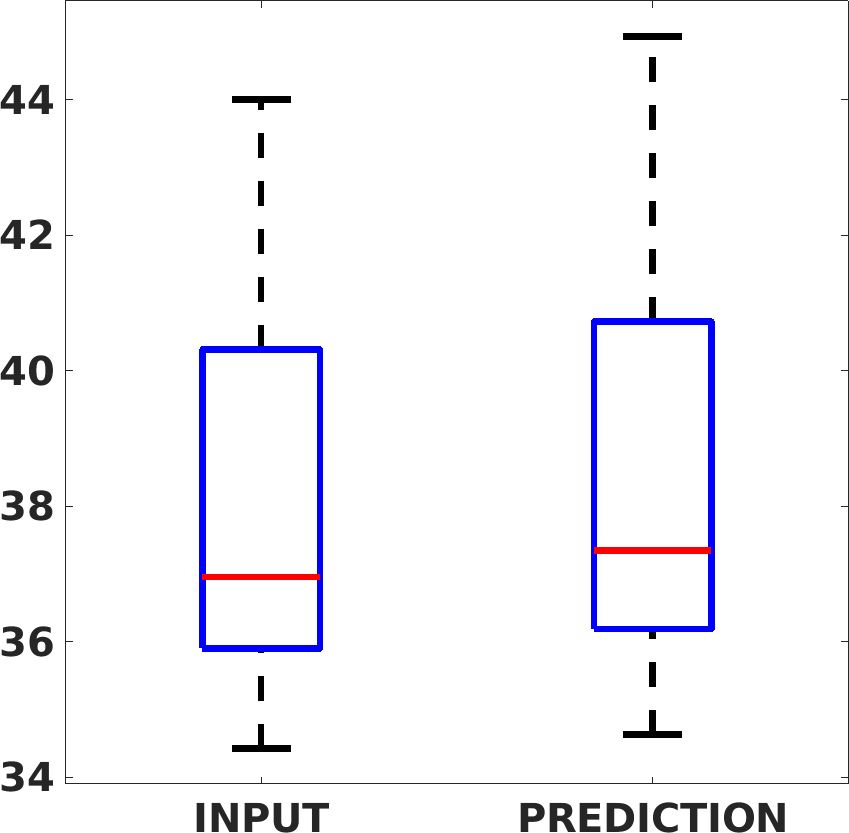

Fig. 8 shows the box plot of the SSIM (a-b-c, left) and MAE (a-b-c, right) quantitative metrics, as performed for PSNR metric. Also, these metrics show that our method improves the results of Cubic convolution both in terms of average value and variability. For example, the SSIM median value improves of on obstetric 4X images and the MAE median value improves of on cardiac 2X images.

Fig. 17 (left) shows the box plot of the quantitative metrics, comparing the target images with the prediction and the Cubic convolution, respectively. The PSNR metric is computed on a data set of 200 images, belonging to the same district, and with the same up-sampling factor. Analysing the obstetric anatomical district and concerning the corresponding raw images (Fig. 7 (a, left)), the denoising allows the network to significantly improve the results of the up-sampling and the prediction. In particular, comparing the target images with the predicted images, the median PSNR value of obstetric 2X denoised images is 51.8, compared to the median PSNR value of obstetric 2X raw images which is 36.9.

Fig. 17 (right) shows the histogram of the absolute value of the error with respect to the target, of the prediction and Cubic convolution respectively. This result shows that our framework increase of and (2X and 4X, respectively) the number of pixels where the prediction error is lower than 5, which is very similar to the target when visually analysing the images, and improved with respect to the learning framework applied to raw images. According to Fig. 18, our method improves the accuracy of Cubic convolution. For example, the SSIM increases of on cardiac 2X and the MAE increases of on abdominal 4X.